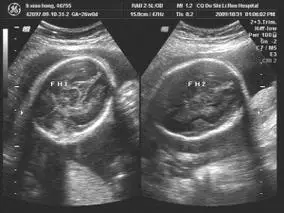

怀孕7月双胞胎竟共用一个心要不要生?37岁准妈妈很痛苦